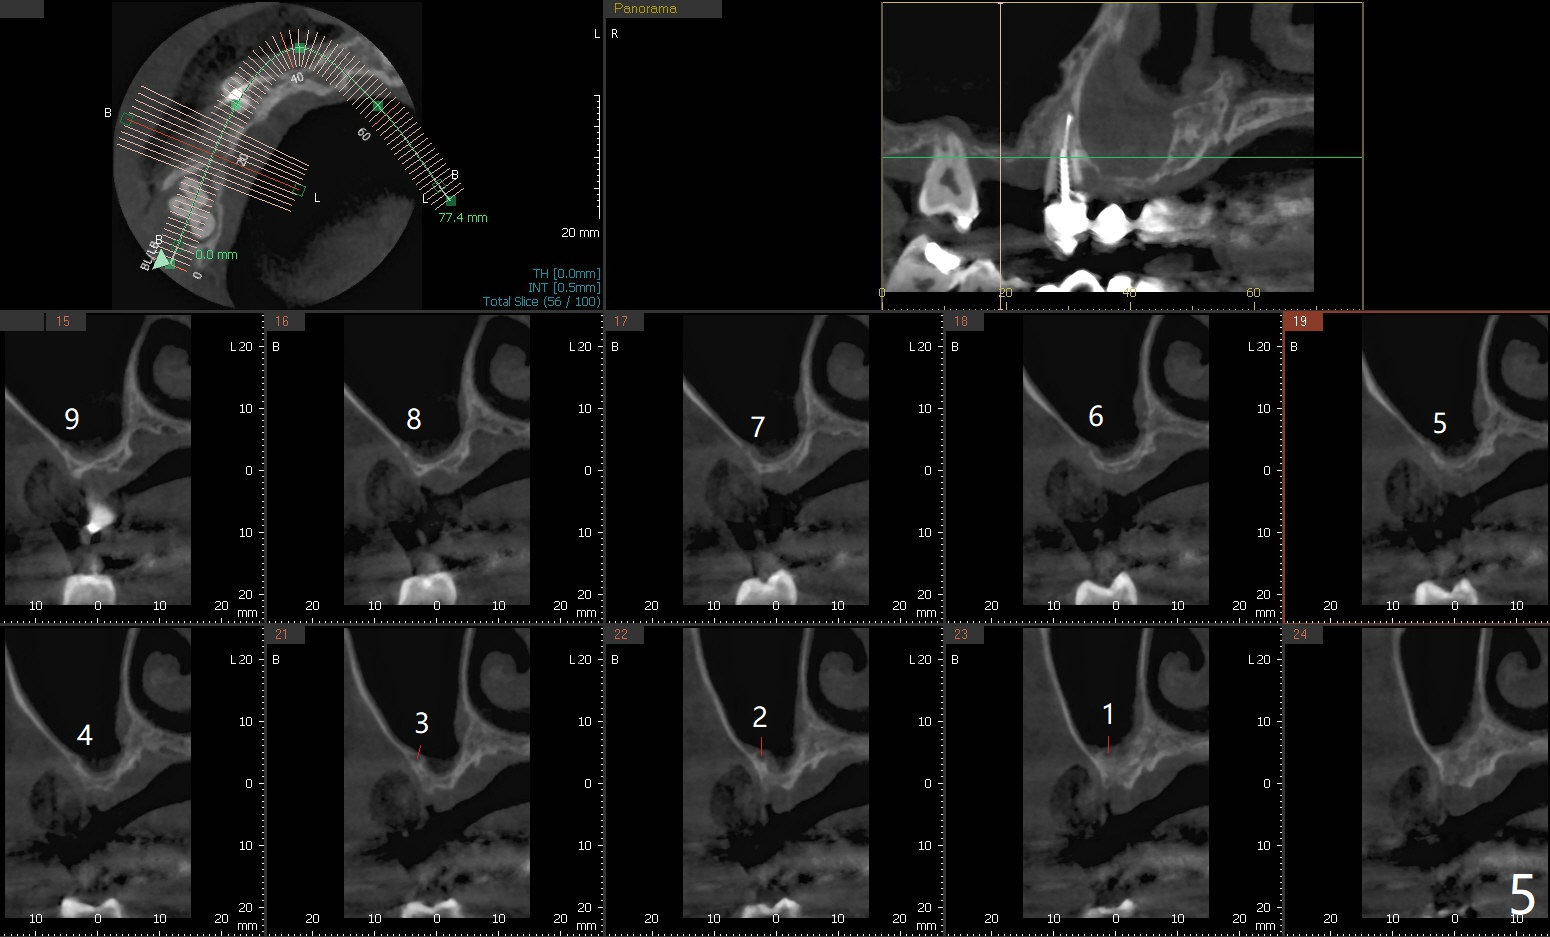

49岁女(图一)同意先做右上5,6种植(图二,三),但是必须先做外提升,高至5根尖(图二:红线),范围延申至右上7,后者骨质吸收厉害(图三:*),预后不佳。后者可能是好几年的事情,是杞人忧天?准备DIO Sinus Master Kit, sinus curettes (curved), a round flat osteotome (in sinus box) and mallet as well as PRFx2。图三黄线代表外提升入口。外提失败因为遇到动脉(图四),上牙槽中血管穿过上颌窦前壁(图五)。实验室建议在右上5种植(图六至八)。结果内提同期种植。